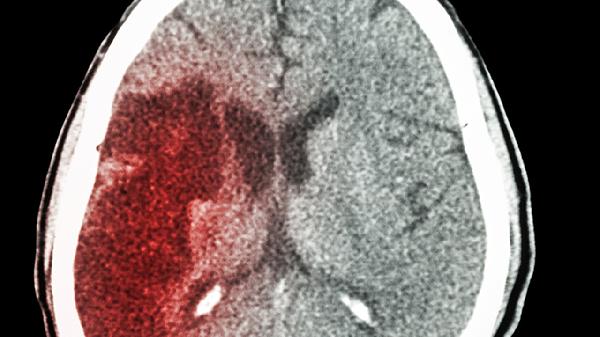

脑梗死和脑溢血是两种不同的脑血管疾病,它们在成因和表现上存在明显差异。脑梗死主要是因为脑部的血管被堵塞,导致局部脑组织缺...